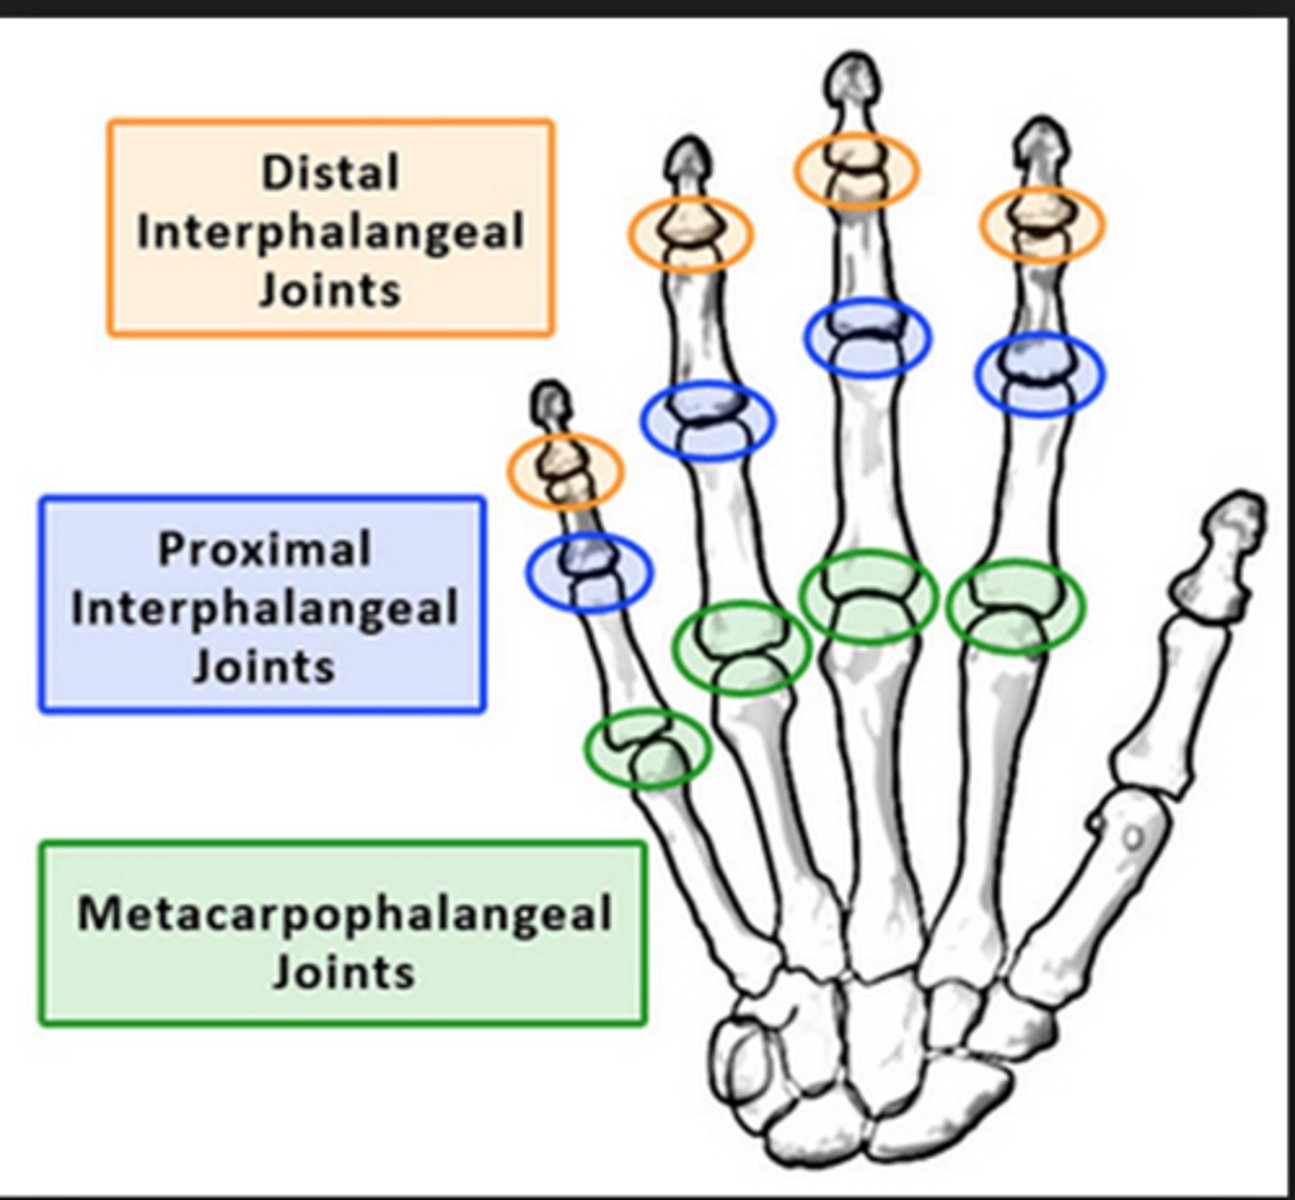

Metacarpophalangeal joints

knuckles; where heads of carpal bones articulate with the proximal phalanges of digits

Proximal interphalangeal joints

between proximal and middle phalanges

Distal interphalangeal joints

Joints between middle and distal phalanges.